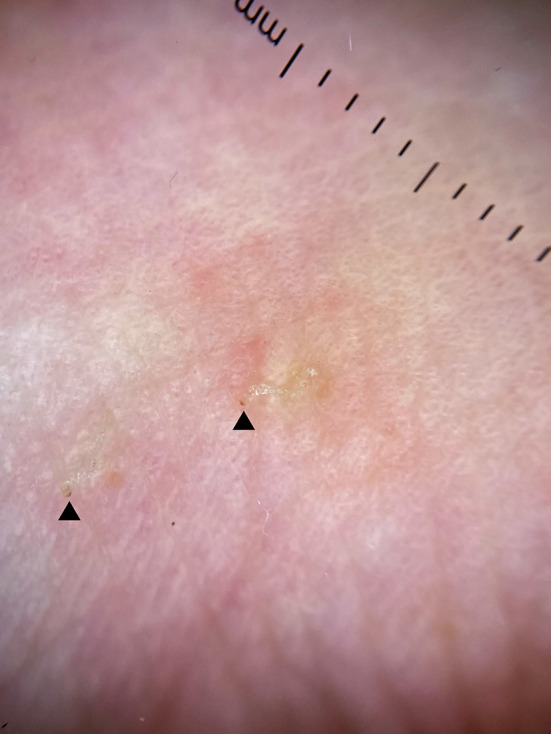

Dermatological examination showed erythematous papules in trunk, legs and arms. Erythematous nodules were present in the scrotum. Mucosae were not affected. With dermoscopy, a scabiotic burrow with the “jet with a contrail” sign and the “triangle” sign was seen in the volar aspect of the left wrist (Fig. 1). We then performed an ultrasound exam with a variable frequency 10–22 MHz lineal probe attached to a MyLabTM9 platform (Esaote). A copious amount of gel was used, and the probe was placed longitudinally along the burrow that we had previously identified with dermoscopy.

Fig. 1.

Dermoscopy of scabiotic burrow with the “jet with a contrail” sign and the “triangle” sign. Arrows mark the “triangle” sign, pointing out the exact location of the mite